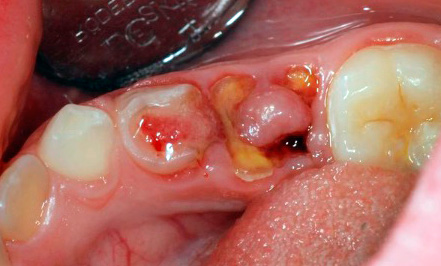

La foto sotto mostra un dente rimosso a causa di complicazioni dopo la pulpite:

Una fotografia di un dente con una cavità profonda e cariata, che in qualsiasi momento può causare pulpite: